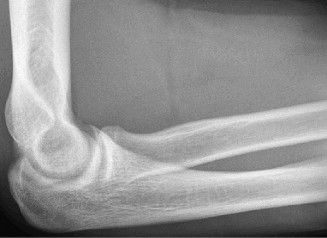

- Radiographs: AP, lateral, and oblique views of the elbow are essential to rule out avulsion fractures, loose bodies, osteophytes, and physeal injuries (in adolescents). Stress radiographs (gravity or manual) can objectively quantify valgus gapping but require expertise to perform and interpret.

- Magnetic Resonance Imaging (MRI): MRI, preferably with an arthrogram, is the gold standard for evaluating UCL integrity, flexor-pronator pathology, and associated intra-articular injuries (e.g., osteochondral lesions). A complete rupture will show discontinuity of the ligament, while a partial tear may show high signal intensity within the substance of the ligament. T2-weighted fat-saturated sequences are particularly useful.